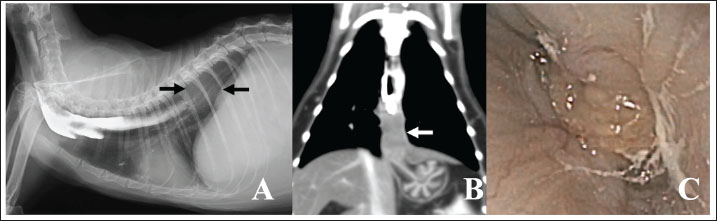

An 8-year-old, spayed, female Japanese domestic cat was admitted to our referring veterinary hospital for evaluation of vomiting/regurgitation that had been occurring for 2 months. The cat had been receiving standard treatment for vomiting at a private hospital, but no clinical improvement was observed. One month before admission to our hospital, the cat’s appetite had decreased, and 4 days before, esophageal contrast radiography was performed at the referring hospital, and esophageal stenosis was suspected. At the time of initial examination at our hospital, the animal was anorexic and had advanced weight loss. The patient’s weight was 2.6 kg; however, according to the owner, the cat weighed more than 5.0 kg before the onset of clinical symptoms. A complete blood count revealed mild anemia, and a biochemical examination revealed hypokalemia and slightly elevated blood bilirubin concentration. Radiographic examination of the thoracic cavity revealed a dilated esophagus with residual contrast medium in the esophagography performed at the referring hospital (Fig. 1A). No contrast medium flowed into the distal third of the esophagus, and a round mass lesion approximately 2 cm in diameter was observed between the discontinuous contrast medium and the diaphragm. Abdominal radiography revealed no abnormal findings. Computed tomography (CT) examination was performed under general anesthesia induced by intravenous injection of 1–2 mg/kg of alfaxalone (Alfaxan; Meiji Seika Pharma) and maintained with sevoflurane (Sevofran; Maruishi Pharmaceutical). On CT images, we observed a mass approximately 2.5 cm in diameter on the cranial side of the diaphragm, which was considered to be part of the esophagus and the possible cause of food regurgitation. The mass showed a slight enhancement on contrast CT images. The three-dimensional reconstructed CT image showed that the mass was continuous with the gastric mucosa (Fig. 1B). In the abdominal CT images, the liver had a substantially lower CT attenuation value than the gallbladder, suggesting the development of hepatic lipidosis possibly induced by long-term starvation (Nakamura et al., 2005). Furthermore, esophageal endoscopy revealed that the mass lesion protruded from the esophageal mucosa (Fig. 1C). The mass was white, had no ulcerative lesions on its surface, and completely obstructed the esophagus lumen, making it impossible to insert the scope into the stomach. Endoscopic tissue biopsy of the mass strongly suggested SCC of the esophagus.

Fig. 1. (A) Thoracic radiography of the cat at first admission. The barium sulfate used for esophagography performed by the referring hospital remains in the cranial two-thirds of the esophagus. Contrast medium did not flow into the distal third of the esophagus, and a circular mass shadow was observed between the part where the contrast medium stopped and the diaphragm (arrows). (B) Three-dimensional reconstructed coronal CT image of the thoracic cavity. The proximal esophagus lumen contains barium sulfate, and a mass in the distal esophagus appears to be continuous with the gastric mucosa (arrow). (C) Endoscopic image of the esophagus showing white tumor tissue bulging from the esophagus wall and completely obstructing the lumen.